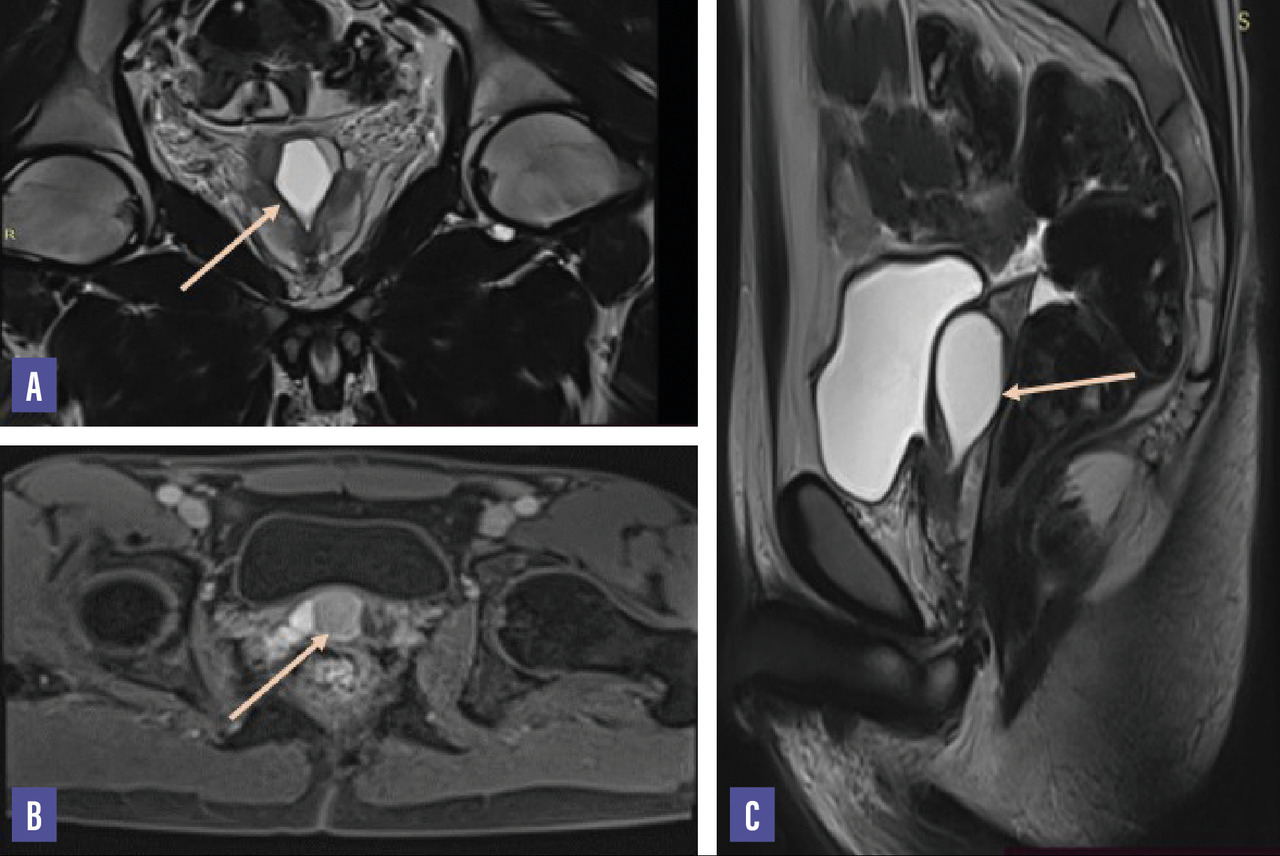

L’imagerie par résonance magnétique (IRM) dévoile la présence d’un kyste prostatique médian bien limité à paroi fine, à contenu hyposignal en pondération T1 et hypersignal en T2 non rehaussé après injection du produit de contraste mesurant 25 × 20 × 32 mm avec une anomalie de signal du contenu de la vésicule séminale droite en hypersignal T1 et hyposignal T2 authentifiant un contenu hématique (fig. 2).

L’imagerie par résonance magnétique (IRM) prend une place de plus en plus importante dans l’exploration de la prostate. L’exploration multiplan est un examen parfaitement adapté à l’étude de la pathologie kystique de la prostate. L’IRM visualise la masse liquidienne en précisant ses dimensions, ses rapports et ses limites. Les kystes à contenu purement liquidien, tels que les kystes des canaux éjaculateurs, ont un signal identique à l’urine, à savoir hyposignal en pondération T1 et hypersignal en T2  ; en cas de contenu hémorragique ou riche en protéines, ces lésions apparaissent en hypersignal T1 et T2.5